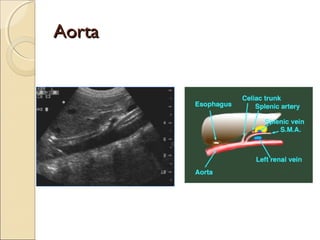

AortaAorta

A nivel EPIGASTRICO:

Hasta 25 mm de diámetro

A nivel UMBILICAL (Mesogastrio)

Hasta 20 mm de diámetro

Calibres entre 25 y 30 mm:

ECTASIAS

Calibres superiores a 30 mm:

ANEURISMAS